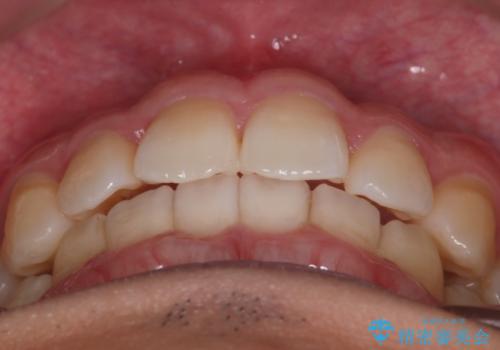

上の前歯が出ているという主訴が綺麗に改善されました。

その他の部位のがたつき、奥歯の噛み合わせも以前と比べると良くなっています。

目立たない装置で治療期間も10ヶ月と短く終了することができました。